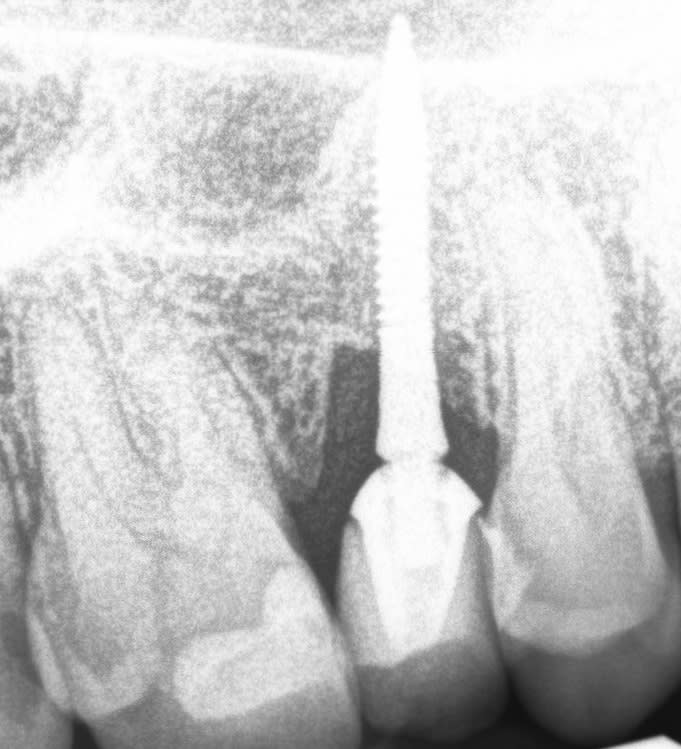

patient de mon prédécesseur en retraite qui se présente cr mobile sur la 15

Apparemment ca me semble être le pilier qui est mobile

En me renseignant je vois que l'implant est un implant intralock Oring housing

Je ne connais pas du tout ce système et j'ai l'impression que l'implant se terminerait par une boule sur lequel le pilier est fixé ?

Sur un système standard j'aurai fait un puit d'acces en occlusal puis revisser le pilier, mais je pense pas que la ca sera possible

Comment gérer ce cas et refixer la couronne ?